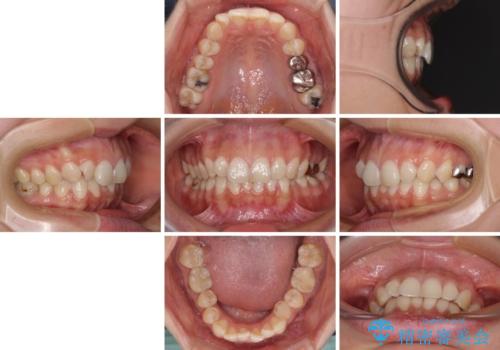

- 下顎の前歯が隠れていることと、デコボコを気にして来院された患者様です。

目立ちにくい装置を希望されていたため、ワイヤー装置とインビザラインを提案したところ、インビザラインを希望されました。

銀歯やムシ歯処置の必要な歯が奥歯にあり気になっていたので、矯正治療の途中でセラミッククラウンへ変更し、その後歯列を仕上げていくこととしました。

咬み合わせと目立っていた銀歯が改善され、患者様には大変満足していただきました。